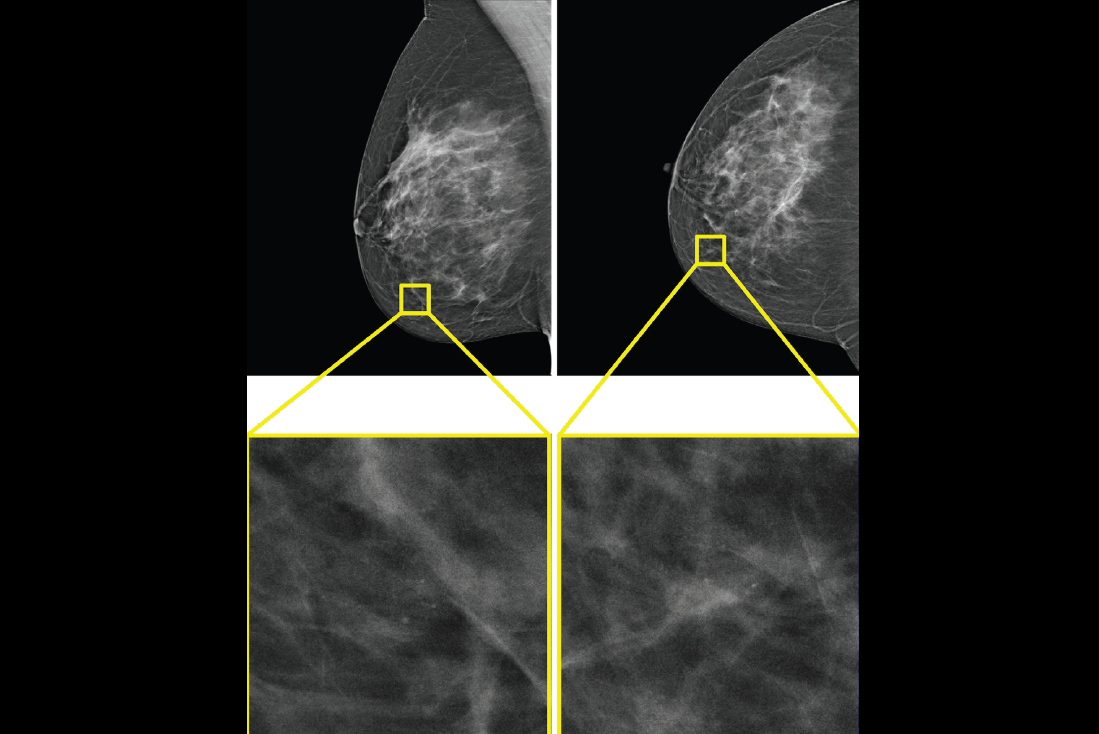

The system’s x-ray diffraction technology measures how x-rays scatter at the molecular level, producing a unique structural signature that reflects the internal composition of breast tissue.

In ex vivo studies of breast tissue, the tissue-specific signatures enabled classification of cancerous and benign samples with four times the precision of conventional imaging techniques, Calidar said.